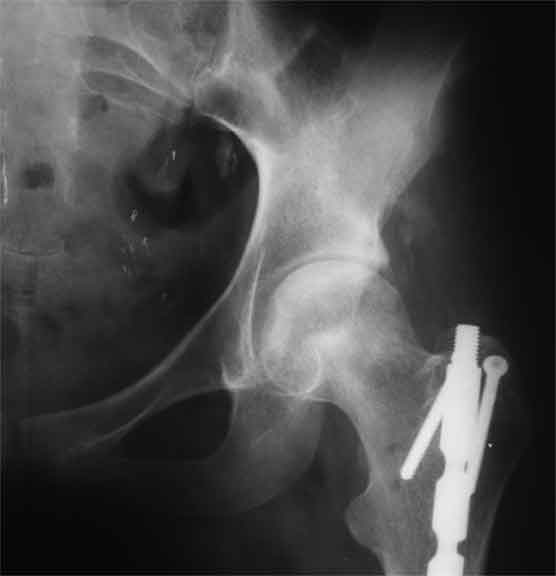

Еще пара фото, ситуация несколько иная, задачи те же, открытое вправление застарелого вывиха в 2002, молодой возраст. Сейчас госпитализирована для эндопротезирования.